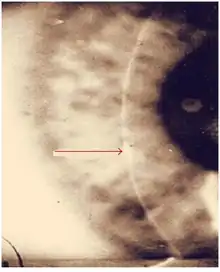

Interstitial keratitis in congenital syphilis | |

Interstitial keratitis (IK) is corneal scarring due to chronic inflammation of the corneal stroma.[1] Interstitial means space between cells i.e. corneal stroma which lies between the epithelium and the endothelium. Keratitis means corneal inflammation.

Acutely, early symptoms include a painful, photophobic, red watery eye. This is due to active corneal inflammation resulting in vascular invasion and stromal necrosis which can be diffuse or localized. This causes the pinkish discoloration of what was a clear transparent normal corneal tissue (called Salmon patch of Hutchinson).

Such vascularization is likely to result in blurring of vision secondary to corneal stromal scarring, the presence of ghost vessels, and thinning of the cornea, especially if it involves the visual axis.

The corneal scarring is the end result of the initial invasion of blood vessels into the corneal stroma as part of the inflammatory response. Since normal corneal tissue should be avascular (no blood vessel) and therefore clear to allow light to pass, the presence of blood vessel and the infiltration of cells as part of the inflammatory process results in scarring or hazing of the cornea.[4]